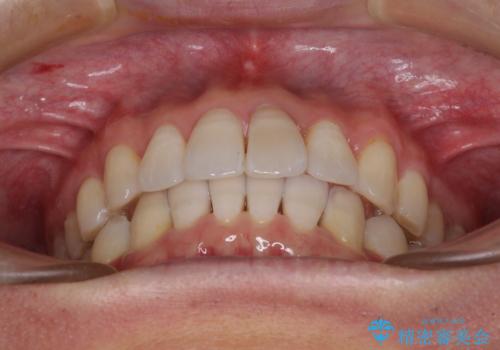

前歯のデコボコを治したい インビザラインによる矯正治療

上下顎ともに歯列全体の後方移動とIPR(歯と歯の間を削る)によってデコボコが解消するように設計し、インビザラインにより治療を行うこととしました。

矯正治療後、前歯の形と色が気になるとのことでしたが、大分前に失活している(神経が取り除かれている)歯であり、その影響で変色しているため、オールセラミッククラウンによる補綴治療をおすすめいたしました。